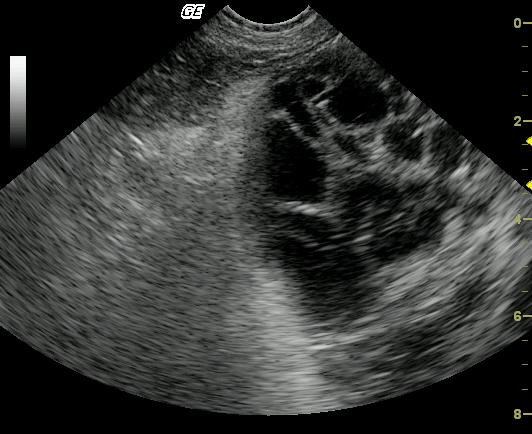

Large cavitated mass with bordering inflammation and suspect omental and mesenteric adhesions. Neoplasia, either benign or malignant arising from a regional soft tissue structure, mesentery or omentum is primarily suspected. Also considered are inflammatory, infectious (parasitic?), granulomatous, hematoma.

A large, well-encapsulated, cavitated and septated mass is present within the peritoneal cavity. The mass is bordered by echogenic omentum and mesentery, which may be adhered. The origin of the mass is not apparent on these images.